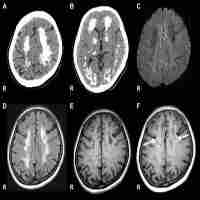

| Abstract | A 18-year-old male, screen printer by profession developed sensory motor polyneuropathy, change in his behavior, bilateral 6th and 7th cranial nerve palsies, down beat nystagmus and cerebellar dysarthria. He had bilaterally prolonged P100 latency; left: 137 ms; right: 144 ms. P 37 was not recordable on either side while N 20 was normal. The inter latency difference between Ipsilateral R2 and Contralateral R2 was 6.15 ms, on the left side and normal on the right side. In the follow-up, there was normalization of the blink reflex study, improvement in P100 latency [left: 114 ms; right: 120 ms.] but worsening of peripheral nerve conductions. The sequential clinical recovery was of the behavioral dysfunction, down beat nystagmus, 6th nerve, 7th nerve involvement and ataxia, in that order. Sural nerve biopsy showed loss of large diameter myelinated fibers. |